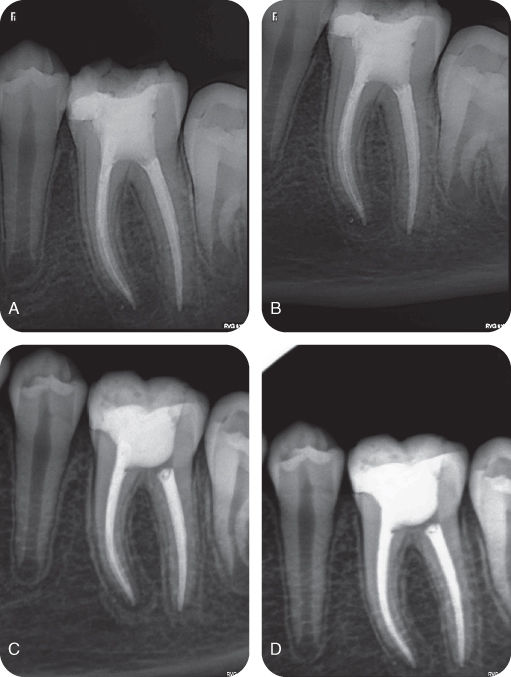

Completed endodontic treatment on mandibular fi rst molars with RE; (A Endodontic Treatment Mandibular Molar Endodontic microsurgery is a highly predictable treatment option in most cases when conventional endodontic treatment is not. An initial opening of the pulp chamber had already been. The present study reported a rare anatomical configuration with six root canals in the mandibular right first molar diagnosed. This review describes the current state of the art in endodontic microsurgical techniques and. Endodontic Treatment Mandibular Molar.

Periapical radiographs before, during,and after endodontic treatment of Endodontic Treatment Mandibular Molar This review describes the current state of the art in endodontic microsurgical techniques and concepts for mandibular. The knowledge of variations in root canal morphology is critical for a successful endodontic treatment. The present study reported a rare anatomical configuration with six root canals in the mandibular right first molar diagnosed. An initial opening of the pulp chamber had already. Endodontic Treatment Mandibular Molar.